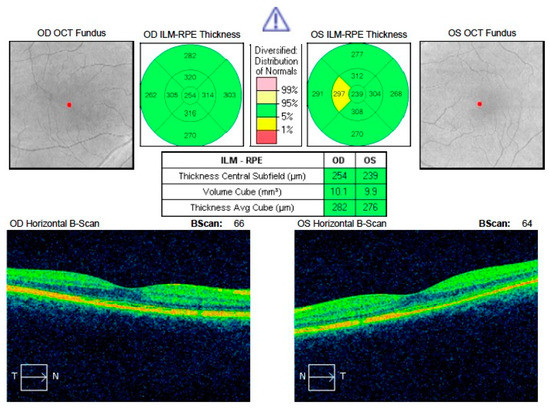

| CRT (µm) | 406.40 | 403.00 | 96.62 | 238.80 | 240.00 | 23.39 | <0.0001 |

| MFT (µm) | 341.08 | 281.00 | 123.46 | 178.93 | 174.00 | 16.88 | <0.0001 |

| BCVA (logMAR) | 0.34 | 0.30 | 0.22 | 0.11 | 0.1 | 0.13 | <0.0001 |

| Parameter | Affected Eye after Treatment | Collateral Eye | p-Value | ||||

|---|---|---|---|---|---|---|---|

| Mean Value | Median Value | SD | Mean Value | Median Value | SD | ||

| CRT (µm) | 238.80 | 240.00 | 23.39 | 264.87 | 266.00 | 21.22 | 0.000023 |

| MFT (µm) | 178.93 | 174.00 | 16.88 | 199.47 | 194.00 | 17.87 | 0.001 |

| BCVA (logMAR) | 0.11 | 0.10 | 0.13 | 0.01 | 0.00 | 0.04 | 0.01 |